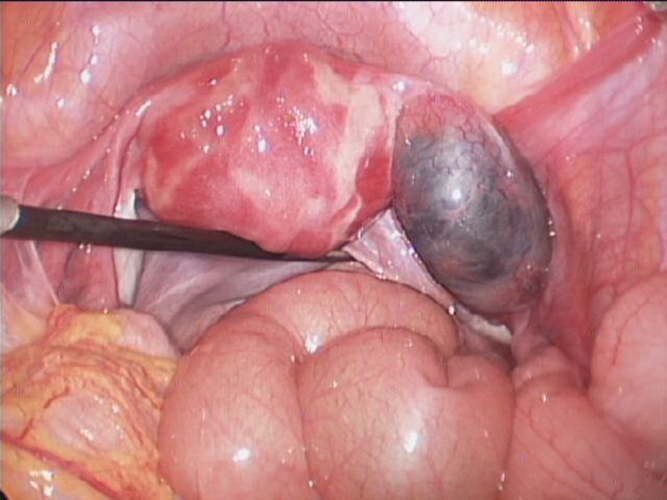

巧克力囊腫圖片

實拍巧克力囊腫